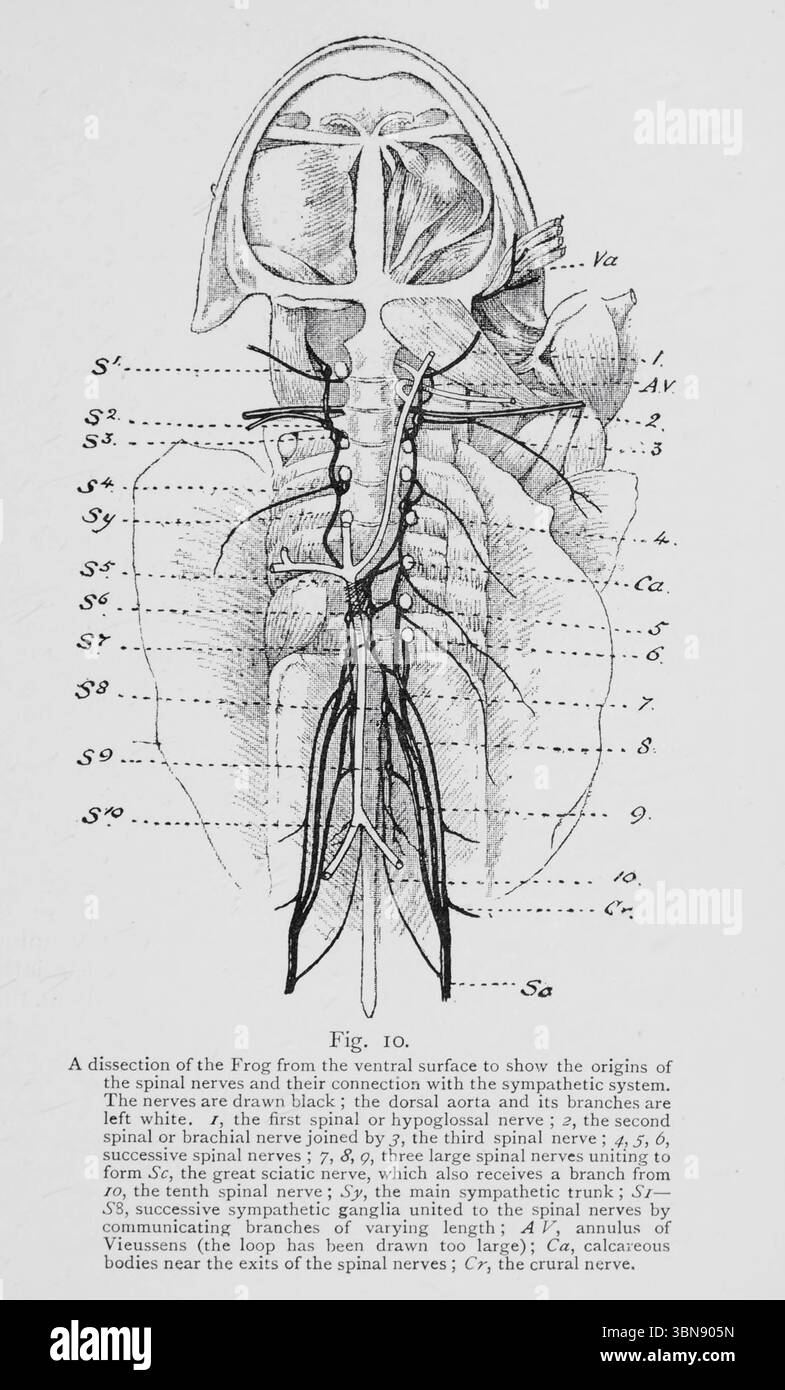

les nerfs rachidiens et leur connexion avec le système sympathique. Les nerfs sont dessinés en noir ; l'aorte dorsale et ses branches sont laissées blanches. /, le premier nerf rachidien ou hypoglosse , 2, le deuxième nerf rachidien ou brachial joint par J, le troisième nerf rachidien 4, 5, 6, les nerfs rachidiens successifs ; 7, 8, g, trois grands ervts spinaux '1' f ? Forme SC, le grand nerf sciatique, qui reçoit également une branche de /o, le dixième nerf spinal ; Sy, le tronc sympathique MAM 6, ganglions sympathiques successifs unis à t e sp a j s QF branches communicantes de longueur variable, Vieussens (la boucle a été Banque D'Imageshttps://www.alamyimages.fr/image-license-details/?v=1https://www.alamyimages.fr/les-nerfs-rachidiens-et-leur-connexion-avec-le-systeme-sympathique-les-nerfs-sont-dessines-en-noir-l-aorte-dorsale-et-ses-branches-sont-laissees-blanches-le-premier-nerf-rachidien-ou-hypoglosse-2-le-deuxieme-nerf-rachidien-ou-brachial-joint-par-j-le-troisieme-nerf-rachidien-4-5-6-les-nerfs-rachidiens-successifs-7-8-g-trois-grands-ervts-spinaux-1-f-forme-sc-le-grand-nerf-sciatique-qui-recoit-egalement-une-branche-de-o-le-dixieme-nerf-spinal-sy-le-tronc-sympathique-mam-6-ganglions-sympathiques-successifs-unis-a-t-e-sp-a-j-s-qf-branches-communicantes-de-longueur-variable-vieussens-la-boucle-a-ete-image684309857.html

les nerfs rachidiens et leur connexion avec le système sympathique. Les nerfs sont dessinés en noir ; l'aorte dorsale et ses branches sont laissées blanches. /, le premier nerf rachidien ou hypoglosse , 2, le deuxième nerf rachidien ou brachial joint par J, le troisième nerf rachidien 4, 5, 6, les nerfs rachidiens successifs ; 7, 8, g, trois grands ervts spinaux '1' f ? Forme SC, le grand nerf sciatique, qui reçoit également une branche de /o, le dixième nerf spinal ; Sy, le tronc sympathique MAM 6, ganglions sympathiques successifs unis à t e sp a j s QF branches communicantes de longueur variable, Vieussens (la boucle a été Banque D'Imageshttps://www.alamyimages.fr/image-license-details/?v=1https://www.alamyimages.fr/les-nerfs-rachidiens-et-leur-connexion-avec-le-systeme-sympathique-les-nerfs-sont-dessines-en-noir-l-aorte-dorsale-et-ses-branches-sont-laissees-blanches-le-premier-nerf-rachidien-ou-hypoglosse-2-le-deuxieme-nerf-rachidien-ou-brachial-joint-par-j-le-troisieme-nerf-rachidien-4-5-6-les-nerfs-rachidiens-successifs-7-8-g-trois-grands-ervts-spinaux-1-f-forme-sc-le-grand-nerf-sciatique-qui-recoit-egalement-une-branche-de-o-le-dixieme-nerf-spinal-sy-le-tronc-sympathique-mam-6-ganglions-sympathiques-successifs-unis-a-t-e-sp-a-j-s-qf-branches-communicantes-de-longueur-variable-vieussens-la-boucle-a-ete-image684309857.htmlRM3BN905N–les nerfs rachidiens et leur connexion avec le système sympathique. Les nerfs sont dessinés en noir ; l'aorte dorsale et ses branches sont laissées blanches. /, le premier nerf rachidien ou hypoglosse , 2, le deuxième nerf rachidien ou brachial joint par J, le troisième nerf rachidien 4, 5, 6, les nerfs rachidiens successifs ; 7, 8, g, trois grands ervts spinaux '1' f ? Forme SC, le grand nerf sciatique, qui reçoit également une branche de /o, le dixième nerf spinal ; Sy, le tronc sympathique MAM 6, ganglions sympathiques successifs unis à t e sp a j s QF branches communicantes de longueur variable, Vieussens (la boucle a été